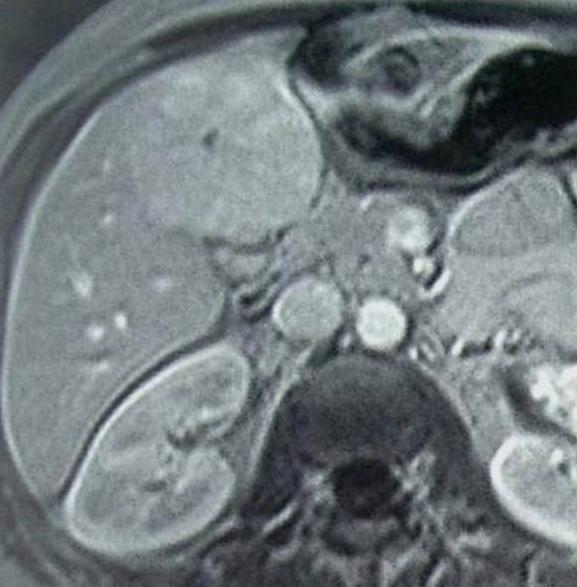

Very variable appearence forms can be observed by US and CT examinations from the early cyst in active phase to the cyst of the died parasite with a calcified wall (although the calcium appearing in the wall of the cyst does not mean that the parasite has unambiguously consumed) in case of an E. granulosus infection (Figure 15).

Figure 15: Echinococcus cyst in the liver, contrast enhanced CT

On the other hand, the liver parenchyma affected by E. multilocularis appears as areas with irregular contour and mixed echogenecity (US) or density (CT) including a hypoechoic (US) or hypodens (CT, this is already the necrotic area) necrotic center (multilocular cyst with inner matrix).